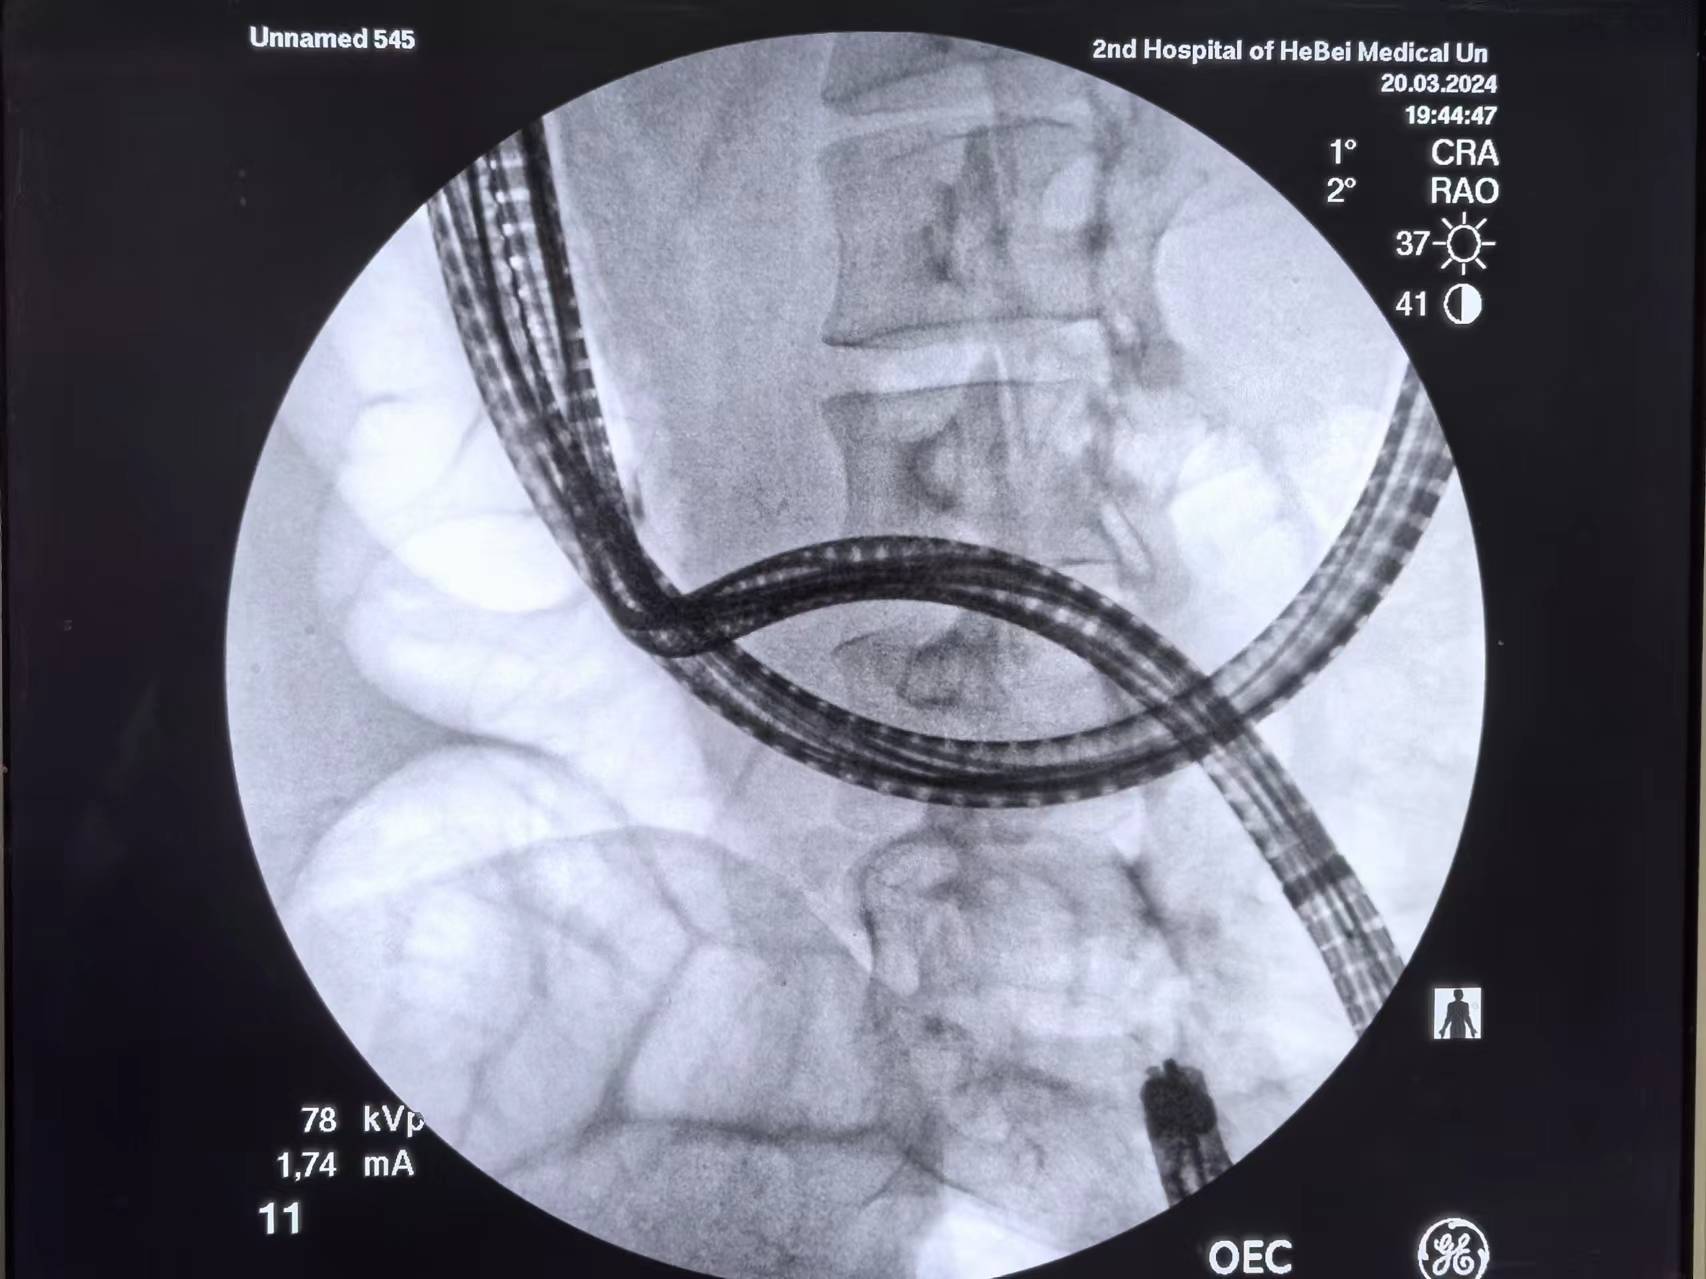

拟行ERCP,肠肠吻合口处成角比较锐利,用了一个半小时镜身到达胆肠吻合口(也备了EUS-BD)

x线下看到肝内胆管显影